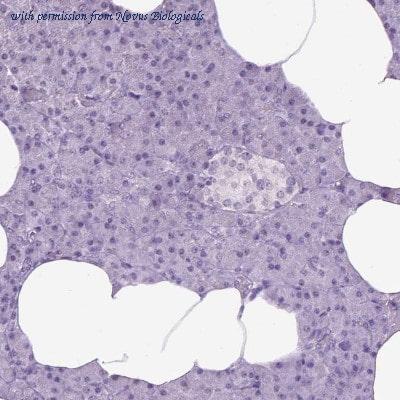

gene information - human kynurenine 3 monooxygenase

- description:kynurenine 3-monooxygenase